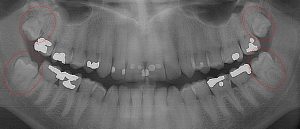

This 34 year old patient has all four third molars present (circled) and fully erupted into occlusion. They appear disease free…but are difficult to keep clean. 3rd molars are the most likely teeth to decay or have gum disease with a >98% probability that decay and gum disease will occur around all four teeth over this patient’s life time.